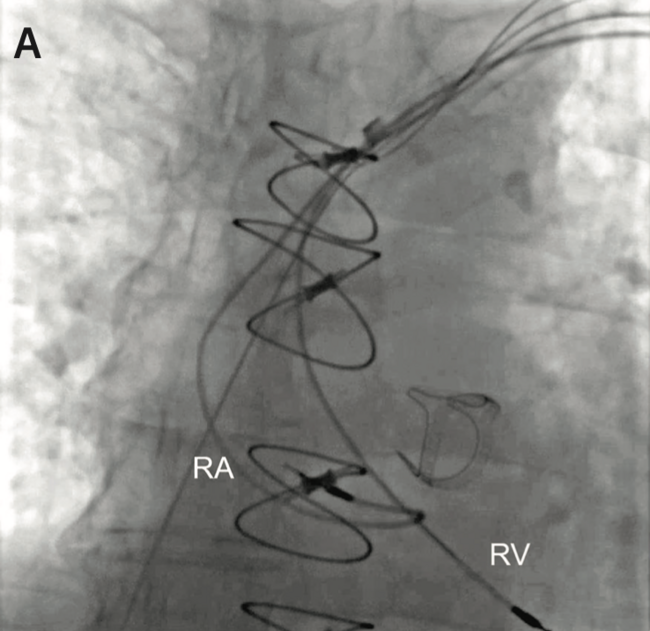

In the first case, the malfunctioning RV lead (active fixation, dwell time 13 years) was extracted using a laser sheath (Figure 1, Video 1). New RV and LV leads were implanted. In the second case, the malfunctioning ICD RV lead (active fixation, dual-coil, dwell time 5 years) was successfully extracted using a laser sheath, which enabled securing venous access for implantation of the new lead. Extraction of the abandoned RV lead (active fixation, dwell time 17 years) was attempted; however, after advancing the laser sheath over the lead within the subclavian and innominate veins, the lead remained tightly bound to the wall of the SVC and could not be freed with manual traction at that point. When laser application at the SVC-RA junction appeared to be necessary for lead removal, extraction efforts were halted and the lead was abandoned. The locking stylet was cut and a protective cap was placed at the proximal end of the lead, which was sutured to the underlying pectoral muscle sheath. In the third case, the malfunctioning RA lead and the abandoned RV lead (both leads were active fixation, 14 years dwell time) were successfully extracted using a laser sheath, and a new RA lead was implanted (Figure 2, Video 2). All patients recovered well without complications and were discharged after a few hours of monitoring.

Video 2. Fluoroscopy anteroposterior views of atrial and ventricular pacing leads before (A) and after (B) extraction in Case 3.